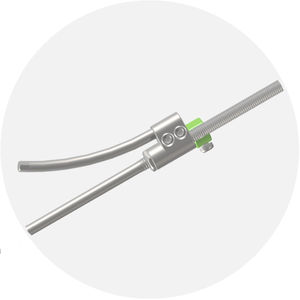

... Para varilla de 6,0 mm y 6,35 mm Sistema de bloqueo DOVETAIL con RANURA LINEAL El exclusivo diseño de rosca de cola de milano permite una fácil inserción a la vez que reduce la posibilidad de roscas cruzadas. La ranura lineal del tornillo ...

... Enganche seguro del instrumento: Características de enganche lateral y superior del instrumento. rango de movimiento cónico de 50 Tornillo de fijación resistente a la separación y a la rosca cruzada Doble núcleo y doble rosca: Inserción eficiente, ...